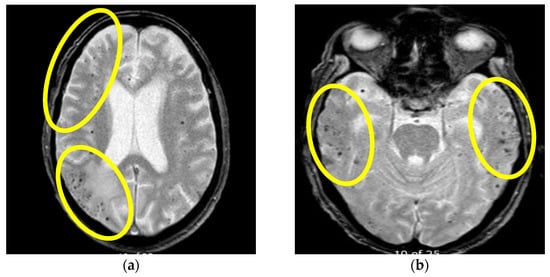

Figure 3.

Initial brain MR axial T2W sequence (a) and control MR examination three months after therapy initiation (b): (a) showing bilateral confluent hyperintense lesions, parieto-occipitally and temporally located in the cortex, subcortically and periventricularly, (b) shows confluent lesions subcortically, in the left temporal lobe in progression in comparison with previous images one month after therapy initiation. Yellow arrows showing confluent hyperintensities on the right parietally and on the left temporally (Patient No. 2).

Figure 4.

Initial MR axial T2*W sequence (a) and control MRI one month after therapy initiation (b): (a) showing bilateral multiple punctiform hypointensities supratentorially, representing deposits of hemosiderin on the first MR examination, (b) showing the persistence of bilateral multiple punctiform hypointensities supratentorially. Yellow circles are showing the bilateral location of the multifocal hypointensities (Patient No. 2).

Based on these findings a diagnosis of probable CAA-rI was established. Initially, pulse methylprednisolone (1 g/daily) therapy was administered for 5 days, followed by oral prednisone (1 mg/kg), slowly tapered down during the next 3 months. During the immunosuppressive treatment, our patient had a verified septic state but was successfully treated with intravenous antibiotic therapy. The follow-up MR examination one month after treatment initiation showed mild progression of the WMH lesions with the persistence of previously noted microbleeds (Figure 3 and Figure 4). Although her neurological examination was without focal neurological deficit, the patients was still complaining about the presence of headaches and her control neuropsychological assessment was mildly improved from the initial mini-mental state examination (MMSE) 22/30 to MMSE 23/30. Thus, treatment with oral prednisone (10 mg/daily) was reintroduced. The third follow-up MR examination after six months showed resolutions of the WMH lesions (not shown), while her neuropsychological assessment was further improving.